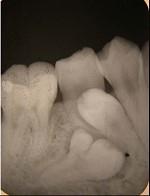

问题 融合牙是()

选项 A.仅见于乳牙 B.仅见于恒牙 C.两牙牙釉质相连 D.两牙牙本质相连 E.两牙牙骨质相连

答案 D